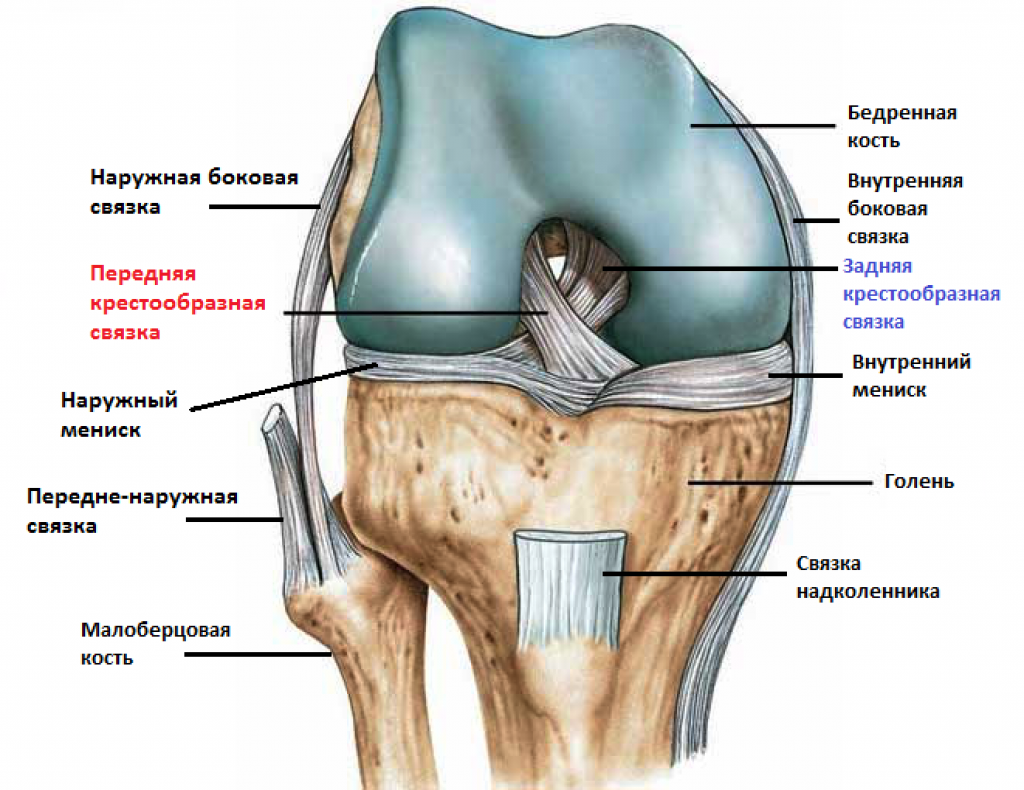

Строение коленного сустава. Повреждения мениска. Разрыв крестообразной связки. Гончаров Е.Н.

Разрыв заднего рога медиального мениска Доктор Мясников Обрезка 01